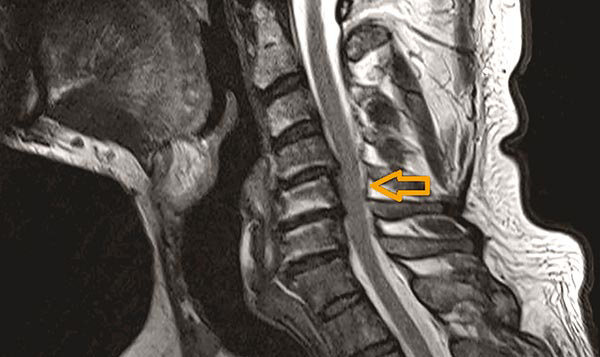

Einengung der neuroforamina therapie. Einengungen des Wirbelkanals sind angeboren oder degenerativ durch Verschleiß erworben meistens besteht eine Kombination beider Ursachen. Der Begriff der zervikalen Spinalkanalstenose beschreibt eine Einengung des Wirbelkanals im Bereich der Halswirbelsäule HWS. Der Arzt nutzt den Begriff konsekutiv um die eingeengte Öffnung mit der Ursache für die Einengung in Verbindung zu bringen.

Wenn die Öffnungen zwischen den Wirbeln eingeengt sind dann besteht eine Einengung der Neuroforamina. Meist nämlich in etwa neun von zehn Fällen reicht im Fall einer Bandscheibenprotrusion eine konservative Therapie aus um Schmerzfreiheit zu erzielen. Es kommt somit zu einer Diskrepanz zwischen der Größe des Rückenmarks Myelon und des Wirbelkanals der relativ zu klein wird.

Einengung des Wirbelkanals Praxis für Neurochirurgie Dr. Bei der Operation von vorm wird der eiengende Wirbelkörper entfernt und durch einen metallischen Platzhalter ersetzt. Kommt es jedoch zu einer schleichenden Verschlechterung der Symptome ist die operative Freilegung des Rückenmarks die Therapie der Wahl um das Fortschreiten der Erkrankung zu stoppen.